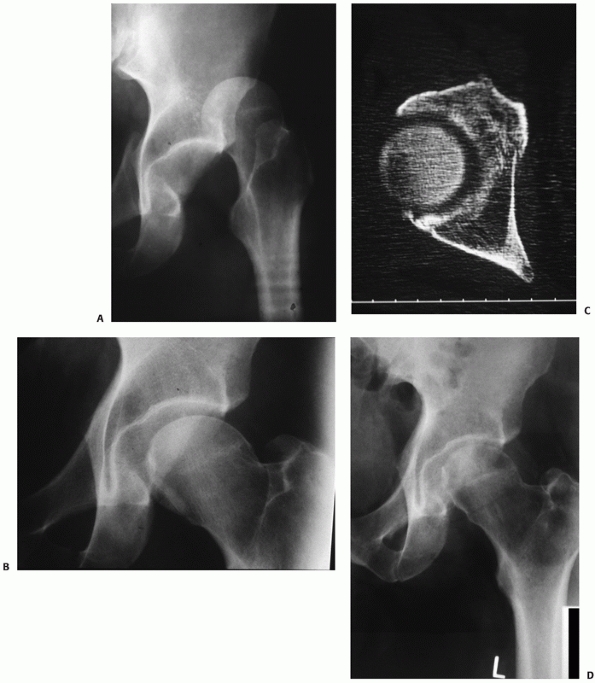

In anterior dislocations, femoral head impaction injuries are more

common than shearing injuries. These are more apparent on the CT images

than on plain films (Fig. 46-6).

![]() |

|

FIGURE 46-6

AP radiograph of a 16-year-old girl demonstrating an inferior anterior dislocation with greater trochanter fracture and femoral head impaction (A). The superolateral impaction is visualized on the postreduction AP (B), but more clearly seen on the CT (C). After the patient was stabilized, open elevation of the depressed articular surface was performed, using bone graft for support. At 2 years, the head has remodeled and the patient had excellent function (D). (Courtesy of William R Creevy, MD.) |